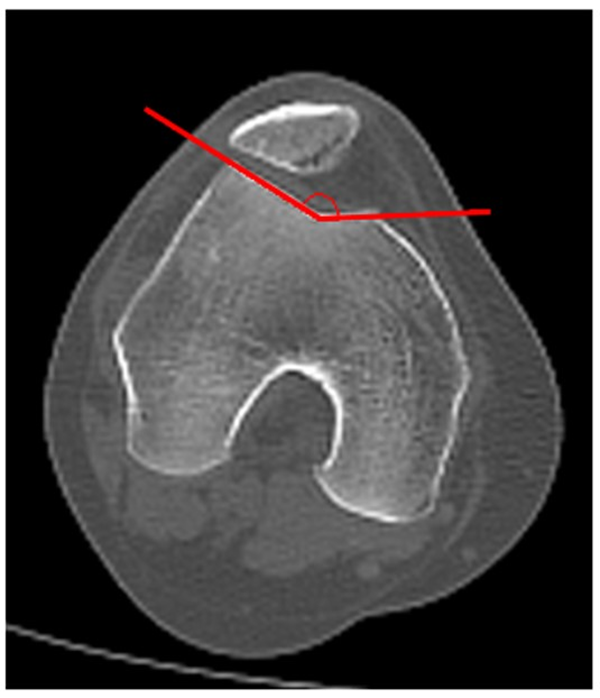

Anteversión femoral (AF)

Esta medición se realiza en extensión completa. En este caso seleccionamos y superponemos dos imágenes axiales según el método descripto por Hernández:16 una donde se observa cabeza, cuello femoral y trocánter mayor, con otra donde se visualiza el corte de la línea bicondílea. El ángulo se forma por la intersección de una línea que pasa por el centro de la cabeza y centro de cuello femoral y la línea bicondílea, de esta manera se obtiene la anteversión femoral. Se expresa en valores positivos cuando es anteversión y negativos cuando es retroversión. Valor normal: 11°,9 (fig. 13).

Figura 13: Anteversión femoral. Se mide con la superposición de dos cortes axiales: uno donde se visualiza cabeza y cuello femoral, y otro, el cóndilo femoral. El ángulo de traza por la intersección de la línea que pasa por el centro de la cabeza femoral y el centro del cuello femoral, con la línea bicondílea. Normal: 11° (8°-15°).